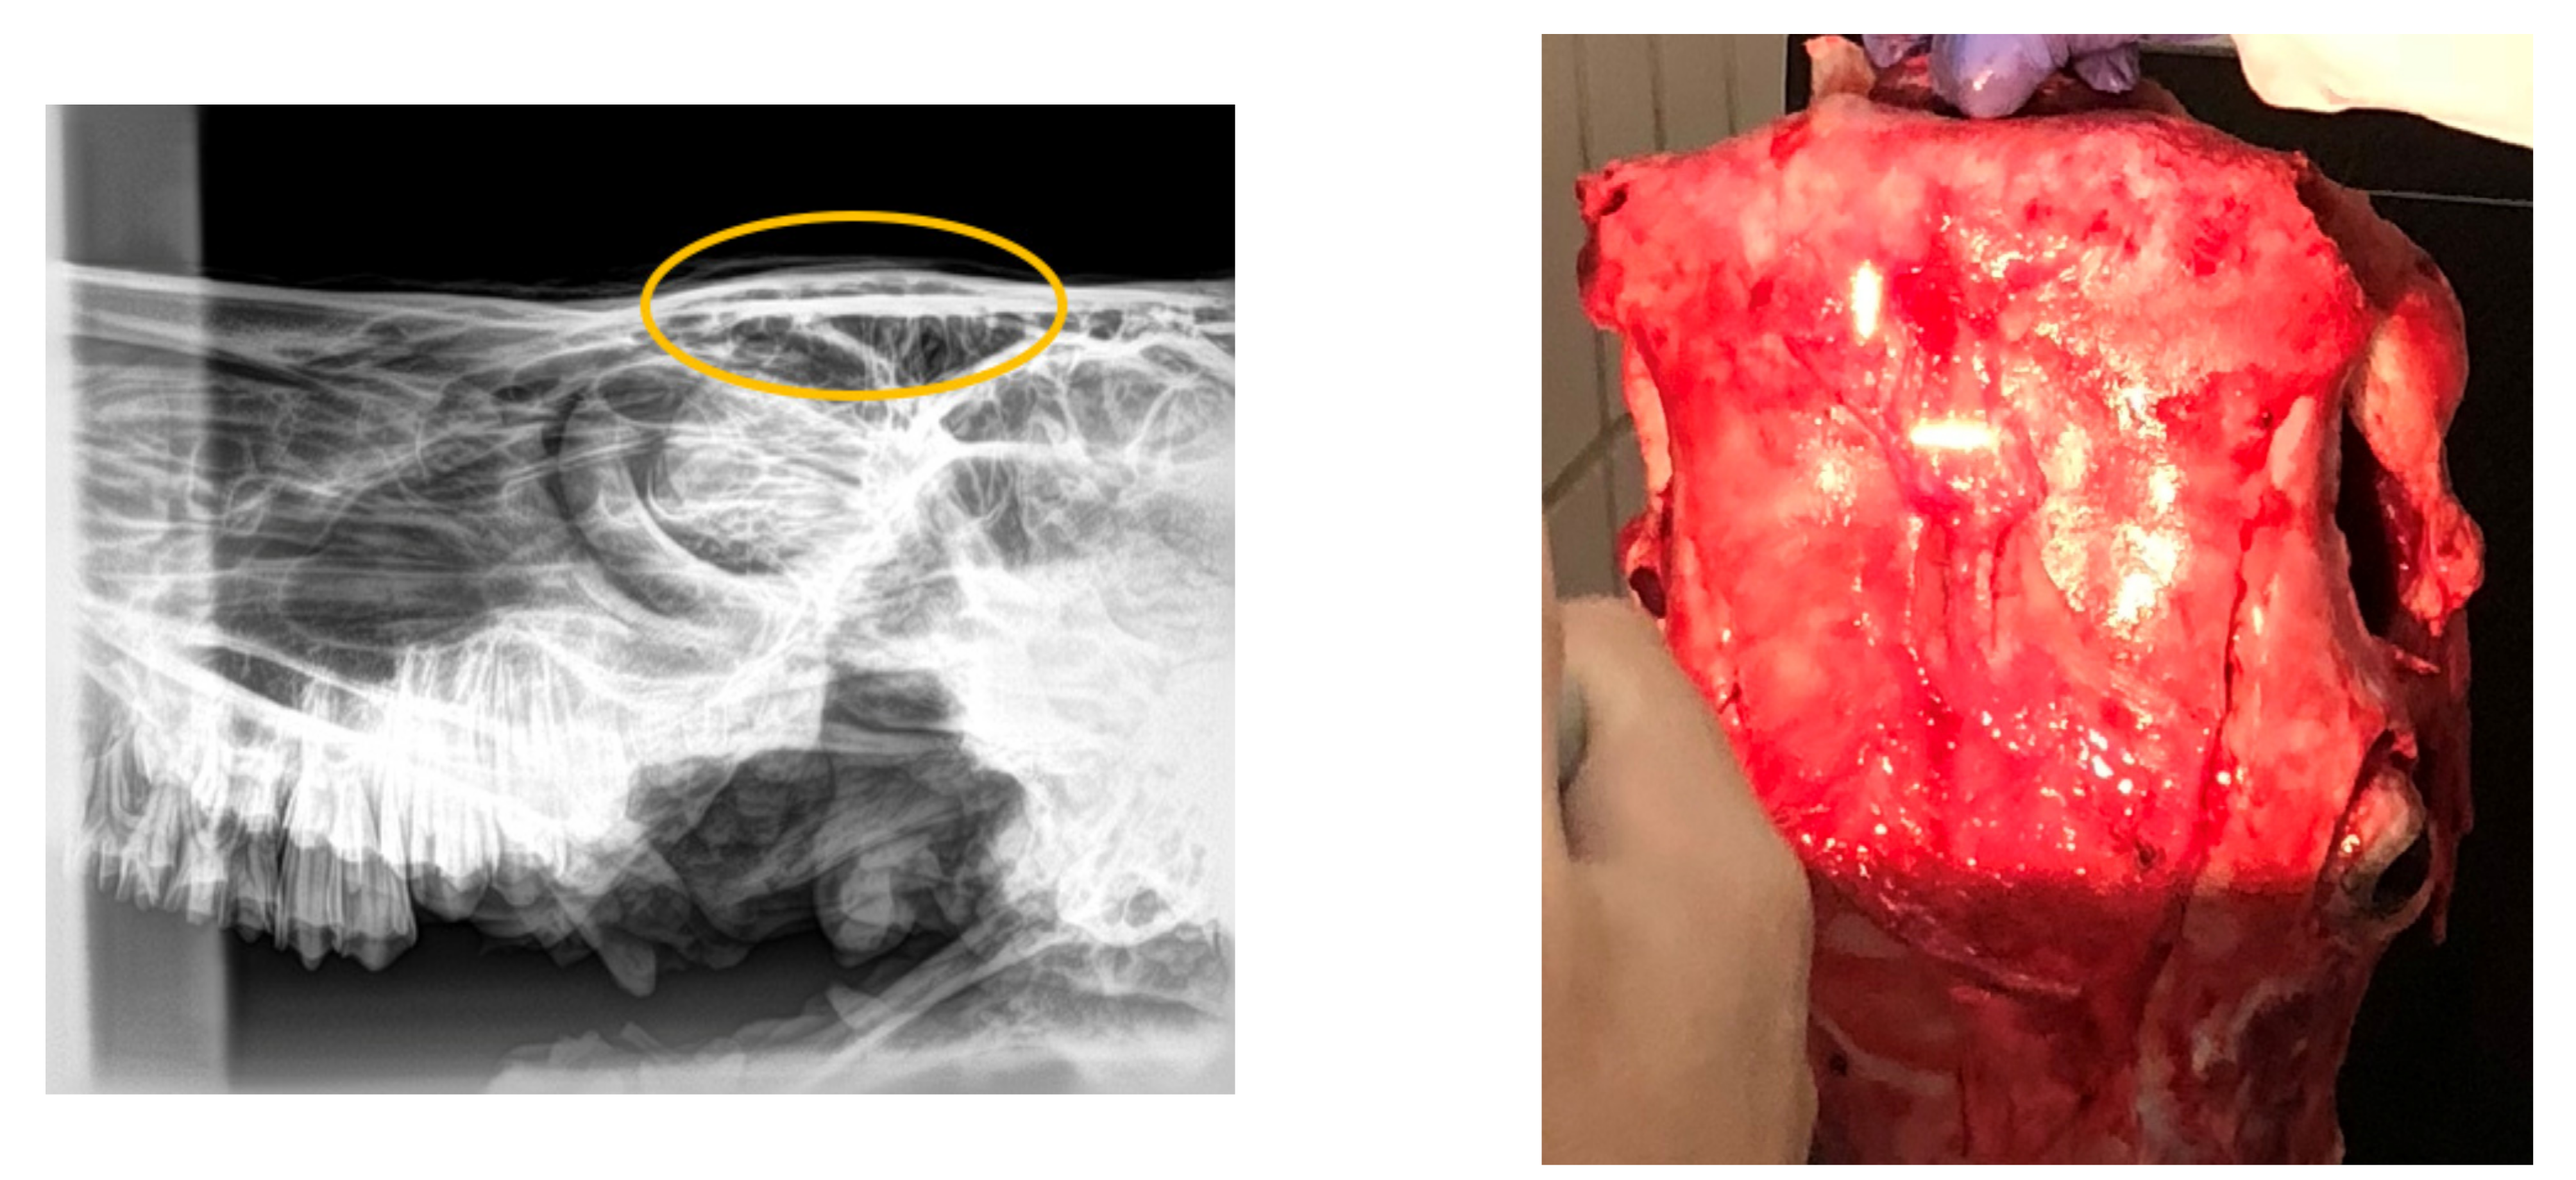

Regarding the radiographical study, it was observed that the skulls presented rating 1 “no visible damage” (70%) or 2 “indentation no cracking” (20%), and rating 3 “indentation with cracking but no displacement” (10%) following the Malaysia Standard (Figure 3, Figure 4, Figure 5). Consequently, 90% of the HSS animals (ratings 1 and 2) would be accepted for halal commercialization. However, no radiographical differences existed between ratings 1 and 2 (Figure 3 and Figure 4); only macroscopic differences in soft tissues were noted.

Figure 3.

Digital radiography rating 1 (following Malaysia Standard 1500:2009), and related photograph.